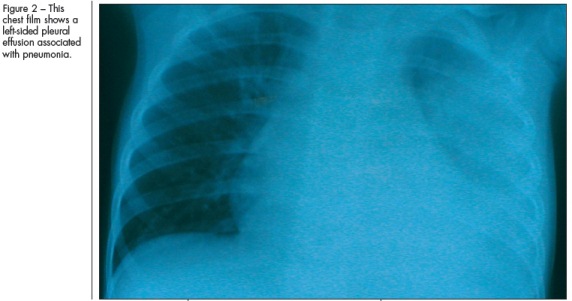

COMPLICATIONSComplications of pneumonia can be local and may occur secondary to the spread of pulmonary infections to contiguous structures (eg, pleural effusion and empyema, pericarditis, and worsening of pulmonary infection leading to formation of a pulmonary abscess) (Figure 2). Complications can also be systemic; they may arise secondary to bacteremia, which can cause meningitis, osteomyelitis, or septic arthritis.

Bacterial pneumonia is the most common cause of pleural effusion or empyema. Pleural effusion can be a part of the clinical spectrum of pneumonia as a synpneumonic effusion, or it may be a complication that leads to an accumulation of pus in the pleural cavity, resulting in an empyema. Patients often have signs and symptoms of pneumonia along with a characteristic pleural rub (especially in small pleural collections), worsening of fever, respiratory distress, decreased air entry on the affected side, dullness to percussion, and mediastinal shift to the opposite side if the fluid accumulation is rapid and significant. These complications are more common in patients with staphylococcal or streptococcal pneumonias and in those who use antibiotics inappropriately or incompletely.

Treatment of children with a complication includes ultrasonograms or chest CT scans for diagnosis, use of antibiotics based on sensitivity patterns, and thoracotomy with tube drainage. Most patients respond to these interventions and rarely require additional interventions such as injection of fibrinolytic agents into the pleural space.